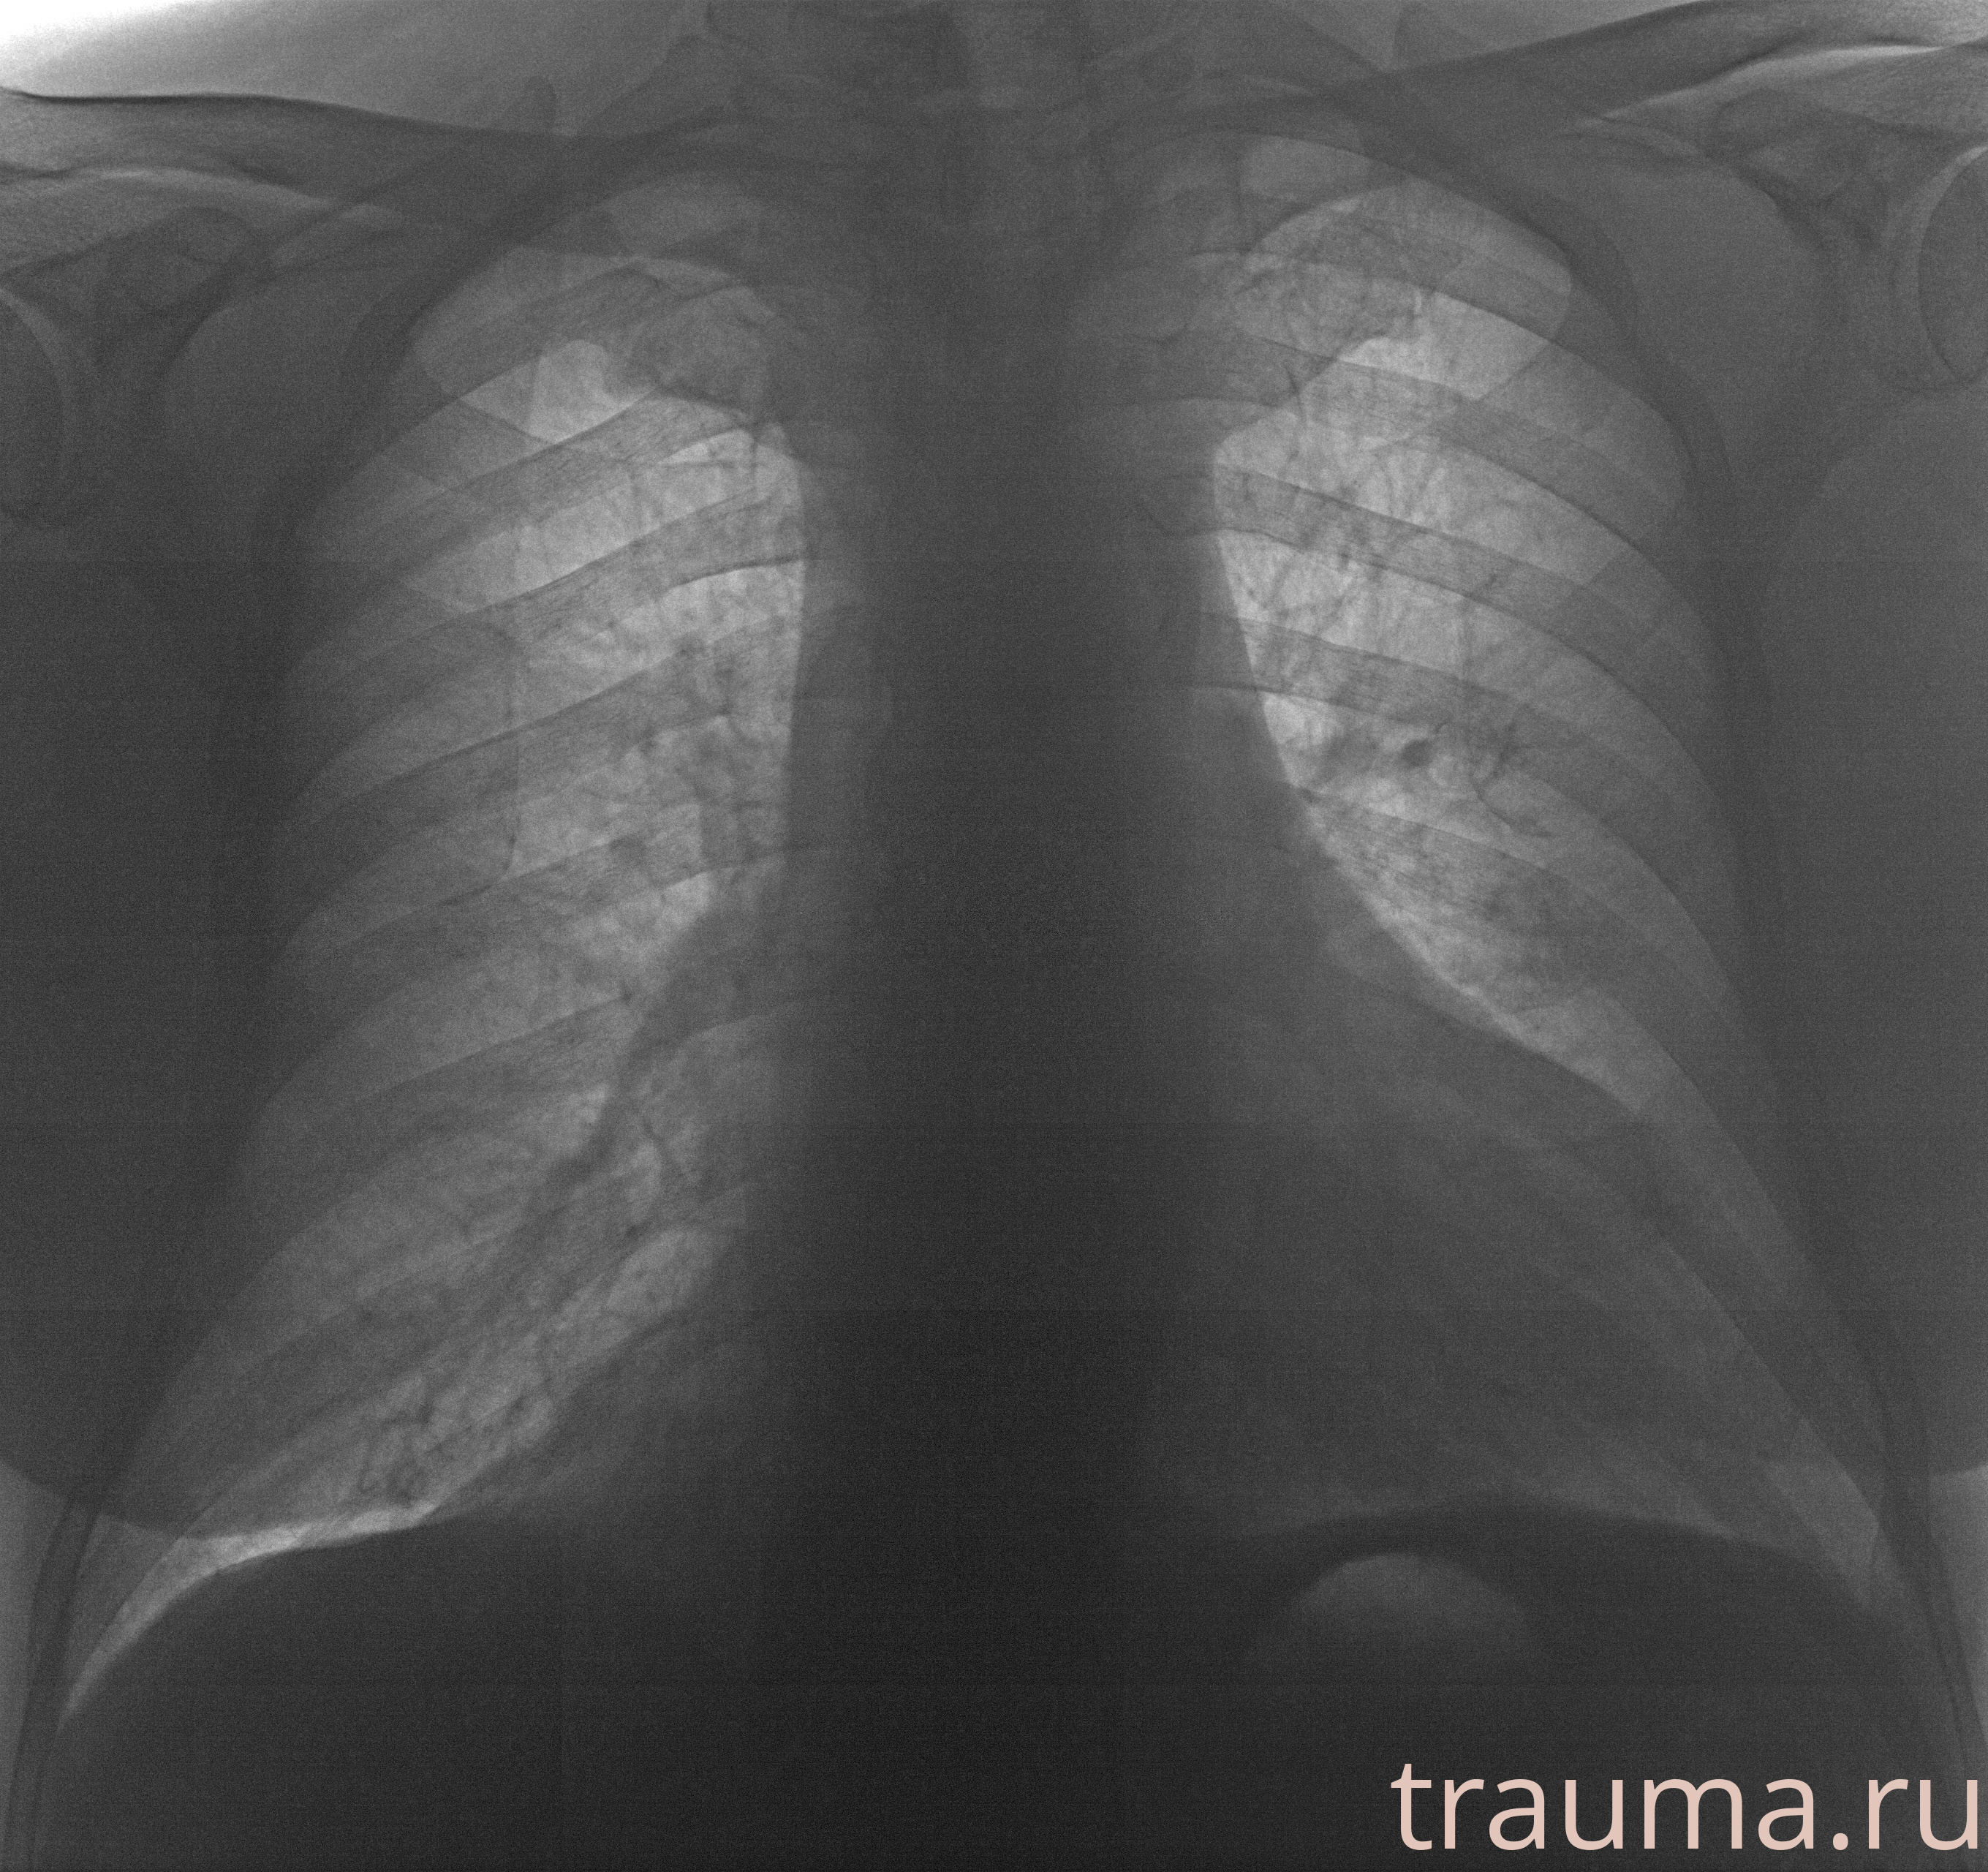

Рентгенограммы

Рентген на дому: по вашему адресу приезжает врач-рентгенолог, травматолог-ортопед с мобильным рентгеновским аппаратом, проводит диагностику травмы или заболевания, делает необходимые рентгенограммы, дает рекомендации по дальнейшему лечению. Получить качественные снимки в домашних условиях возможно благодаря уникальной методике, разработанной МосРентген Центром для института  Склифосовского

при переломе шейки бедра и пневмонии от компании МосРентген Центр - партнера Института имени Склифосовского